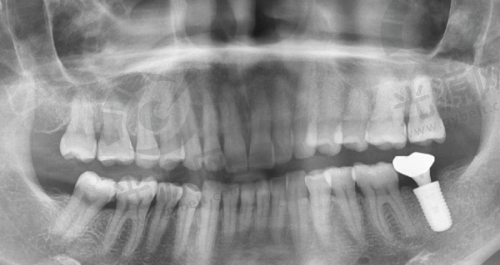

四、唐山地区该项目的技术优势

唐山地区的种植牙技术近年来不断更新,尤其是数字化种植技术和微创种植技术逐渐开始普及。这能有效降低患者的手术风险和修复时间,提高成功几率。